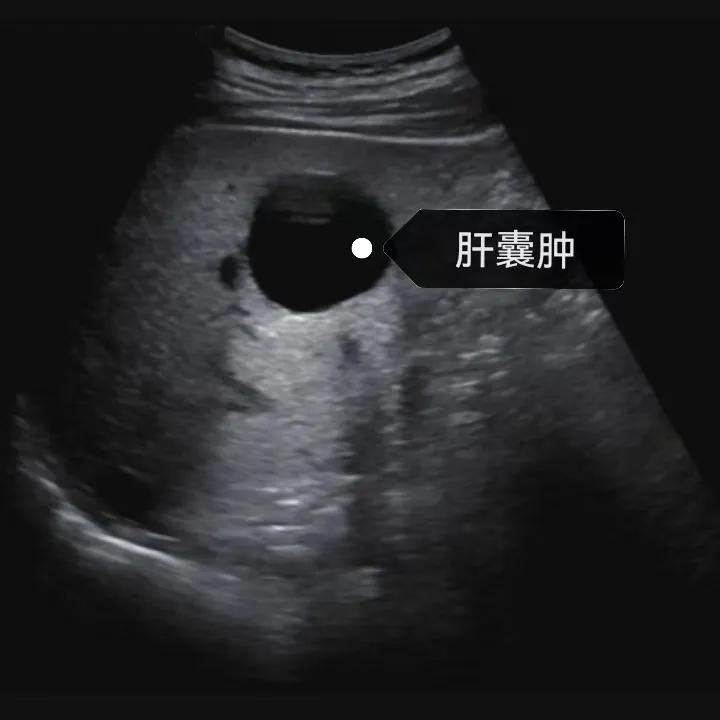

漯河市中醫(yī)院健康科普:認識肝囊腫

隨著人們健康意識的提升,越來越多的人每年會進行健康體檢,由于腹部(肝膽胰脾)超聲作為常規(guī)體檢項目之一, 肝囊腫的檢出率也愈發(fā)升高,大部分人對“腫”字都比較困惑,今天我們就來一起了解一下肝囊腫。

肝囊腫是一種常見的肝臟良性疾病,呈圓形或橢圓形,外由上皮細胞包裹形成包膜,內(nèi)由清亮、無色、無細胞成分的囊液填充,看上去就像是一顆注滿了水的氣球,因此通俗一點說就是肝臟中的“水泡”。

超聲通常是診斷肝囊腫的首選方法,彩超對肝囊腫的檢出率可達98%,<1cm的囊腫也可檢出。肝囊腫常表現(xiàn)為圓形或橢圓形無回聲,包膜光滑完整,邊界清晰,可有側(cè)壁回聲失落征象,后方回聲增強。病程長、囊腫較大者或囊內(nèi)有過出血、感染者,無回聲腔內(nèi)可見少量絮狀回聲漂浮。超聲對肝囊腫的診斷準確而靈敏,且方法簡單、無創(chuàng)、費用低、可重復(fù)性高,因此常常被作為首選。